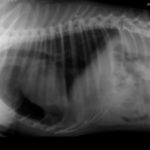

Amigos de Cd del Carmen, es muy triste el caso de Leo A este perrito lo balearon con un rifle en días pasados en Sabancuy, el apoyo para solventar gastos ha sido casi nulo, él se encuentra actualmente internado en la Veterinaria MiCan.

Será trasladado a la Ciudad de Mérida para su cirugía y hacerle extracción de balas, por favor apoyemos el caso con donativos, toda ayuda es bienvenida, se tiene adeudo en la veterinaria y la cirugía saldrá en 15,000.00. Leo se aferra a la vida.